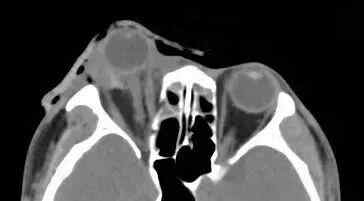

陈先生和朋友聚餐,当晚,喝了酒的他独自散步回家。不料路过一处台阶时,他脚下一空,重重摔在地上。等他回过神来后,发现自己的一只眼睛动不了,也看不见东西,立即前往医院求助。

据厦门眼科中心眼外伤及眼底病二科副主任医师吴东海回忆,接诊时,陈先生的右眼眼球脱出眼眶,肿胀充血,眼睛无法正常闭合。他的视力几乎丧失,眼球上下方都有大面积的结膜裂伤。辅助检查的影像学结果显示,陈先生的伤眼近一半已脱出眼眶,眼球壁上还有星星点点的异物存留。

所幸陈先生视神经、眼外肌肉未发生断裂,眼球壁也未破裂,但他的状况依然危急。为防止角膜长时间暴露,医生立即对陈先生的伤眼做了包扎处理。待陈先生的身体状况稳定后,医生通过手术将陈先生的眼球还纳。